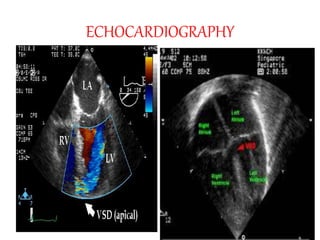

ECHOCARDIOGRAPHY

CHEST XRAY